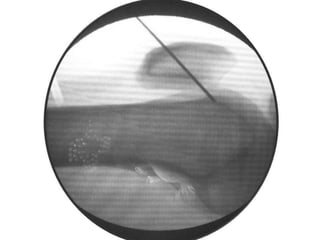

Osteoid Osteoma - Tx

• Excision of the osteoid osteoma nidus using

CT–assisted localization, a Kirschner wire

inserted into the nidus, and a biopsy punch

inserted over the Kirschner wire into the

bone.

• They recommend using a trephine 2 mm

larger than the lesion for complete removal.